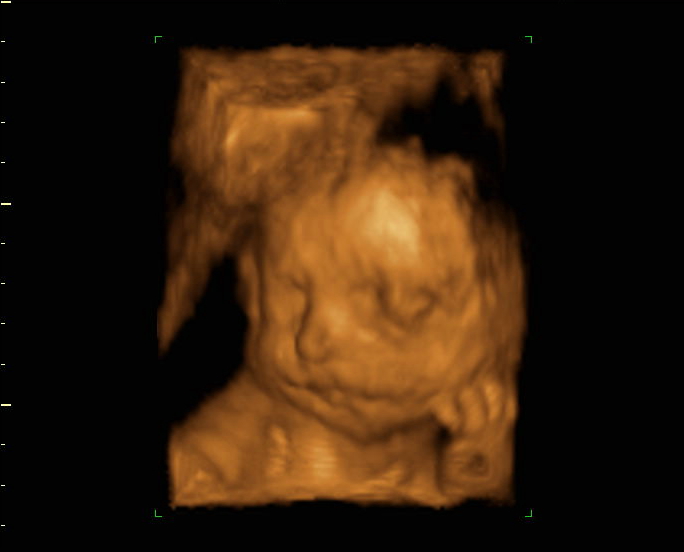

Ich muss auch immer noch an die beiden denken, und das zeigt mir immer, das man sich nicht sicher seien kann, und das schwirrt bei mir im Kopf. Achja der Kleine liegt noch schön in BEL. Dadurch sagt meine Hebi, haben die Füße unten auch nicht viel Platz. Oft rumst es da unten, aber mal tritt er auch den Unterbauch.

28+6 (2).jpg

28+6.jpg

der kleine 28ssw.jpg